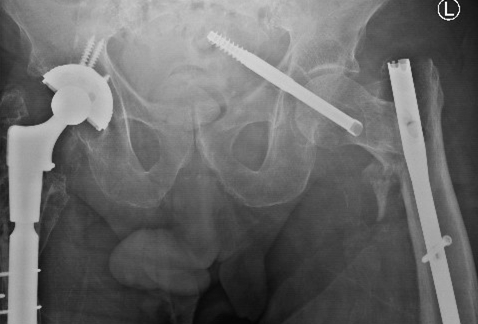

一名 85 岁男性因左股骨转子间骨折接受了短头髓钉固定术。跌倒后,检查显示头髓螺钉从内侧上移位到盆腔中。血管造影显示螺钉尖端位于髂骨分叉处 2 厘米以内,没有出血或内脏损伤的证据。

再次外伤后,拉力螺钉上内侧移位